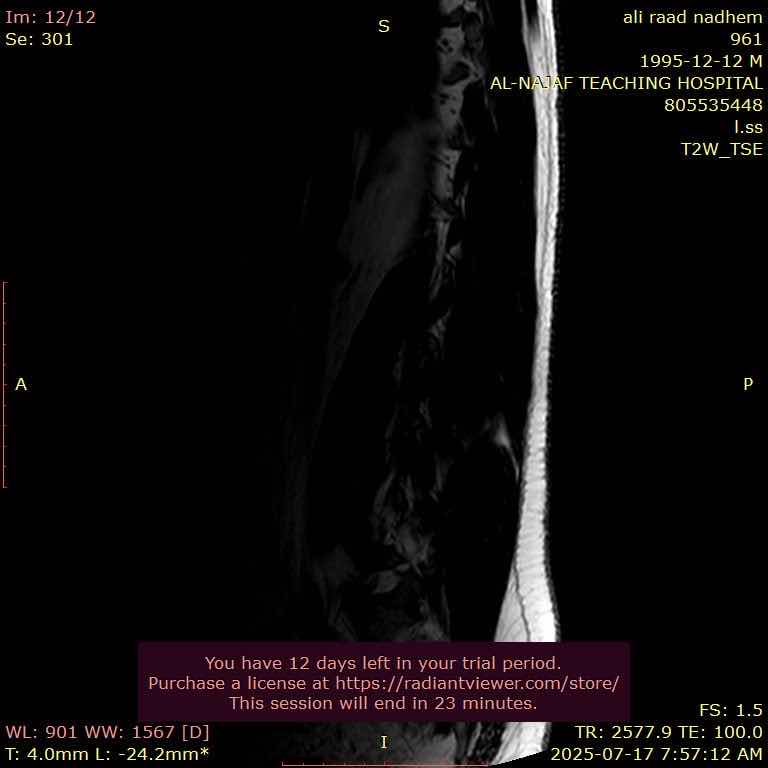

اني عندي انزلاق غضروفي ب3 فقرات اسفل الظهر واريد اراجع دكتور ايهما افضل الي دكتور جملة عصبية او دكتور مفاصل او دكتور كسور

828B877A-5512-472F-90CC-0E3C8F8BAE48 F02F47FA-A8E2-47D8-87B5-78739789E496